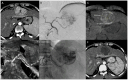

Background: Hepatocellular carcinoma (HCC) is one of the leading cause of cancer death worldwide. Transarterial therapies represent an important tool in the management of different clinical scenarios, from a patient with a single nodule to a patient with multinodular disease. Up to 30% of patients are diagnosed with intermediate-stage HCC, and transarterial chemoembolization (TACE) represents the mainstay of treatment. Overall survival in patients with HCC undergoing TACE is strongly influenced by obtaining a sustained complete response, which is strongly affected by the HCC's dimension. Methods: Pressure gradient-driven embolization, achieved by employing a microballoon catheter in the balloon-occluded TACE (bTACE), represents the most novel innovation in the field of transarterial therapies in the last decade. In fact, bTACE, thanks to its ability to redistribute flow towards tumor territories, can allow higher chemotherapeutic drug concentrations, leading to better oncological performance, especially in patients in which standard TACE struggles to obtain a complete response. Conclusions: This technical and diagnostic intraprocedural step-by-step guide, discussed with a review of the existing literature, will enable readers to achieve an optimal procedure and to convey to their patients the full clinical benefits of these procedures.